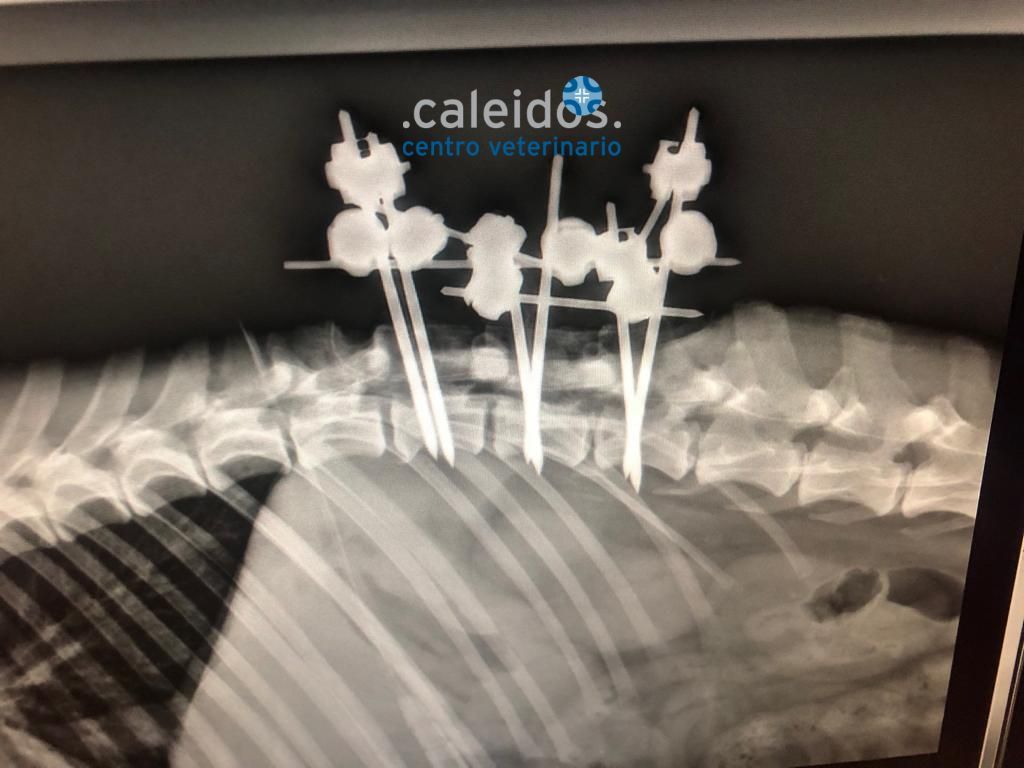

Presso la nostra struttura, potrete sottoporre i vostri animali all'attenzione di neurologi validi e competenti che individueranno la natura e la sede dell'eventuale problema, quindi l'iter diagnostico più adeguato e l'opportuna terapia, che prevede anche l’esecuzione, sempre in sede, di interventi di neurochirurgia, compresi quelli di neurochirurgia intracranica, finalizzati all’asportazione di masse tumorali o anomalie congenite.